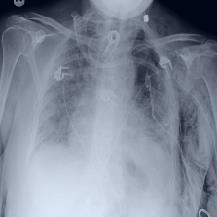

Thoracic disease detection from chest radiographs using deep learning methods has been an active area of research in the last decade. Most previous methods attempt to focus on the diseased organs of the image by identifying spatial regions responsible for significant contributions to the model's prediction. In contrast, expert radiologists first locate the prominent anatomical structures before determining if those regions are anomalous. Therefore, integrating anatomical knowledge within deep learning models could bring substantial improvement in automatic disease classification. This work proposes an anatomy-aware attention-based architecture named Anatomy X-Net, that prioritizes the spatial features guided by the pre-identified anatomy regions. We leverage a semi-supervised learning method using the JSRT dataset containing organ-level annotation to obtain the anatomical segmentation masks (for lungs and heart) for the NIH and CheXpert datasets. The proposed Anatomy X-Net uses the pre-trained DenseNet-121 as the backbone network with two corresponding structured modules, the Anatomy Aware Attention (AAA) and Probabilistic Weighted Average Pooling (PWAP), in a cohesive framework for anatomical attention learning. Our proposed method sets new state-of-the-art performance on the official NIH test set with an AUC score of 0.8439, proving the efficacy of utilizing the anatomy segmentation knowledge to improve the thoracic disease classification. Furthermore, the Anatomy X-Net yields an averaged AUC of 0.9020 on the Stanford CheXpert dataset, improving on existing methods that demonstrate the generalizability of the proposed framework.